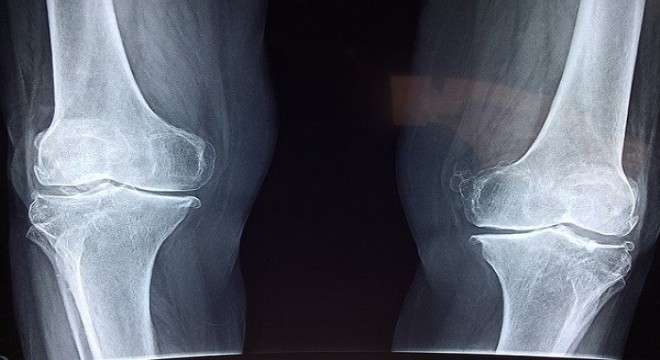

Kemik sağlığını korumak için K2 ve D3 vitamin desteği önemli

Araştırmalara göre; Türkiye’de 50 yaş üzeri her 2 kişiden 1’inde düşük kemik kütlesi, 4 kişiden 1’inde ise kemik erimesi görülüyor.

Diz kapağında eklem kireçlenmesine dikkat

Çömelme ya da merdiven inip çıkma esnasında dizlerinizden gelen sesle ...